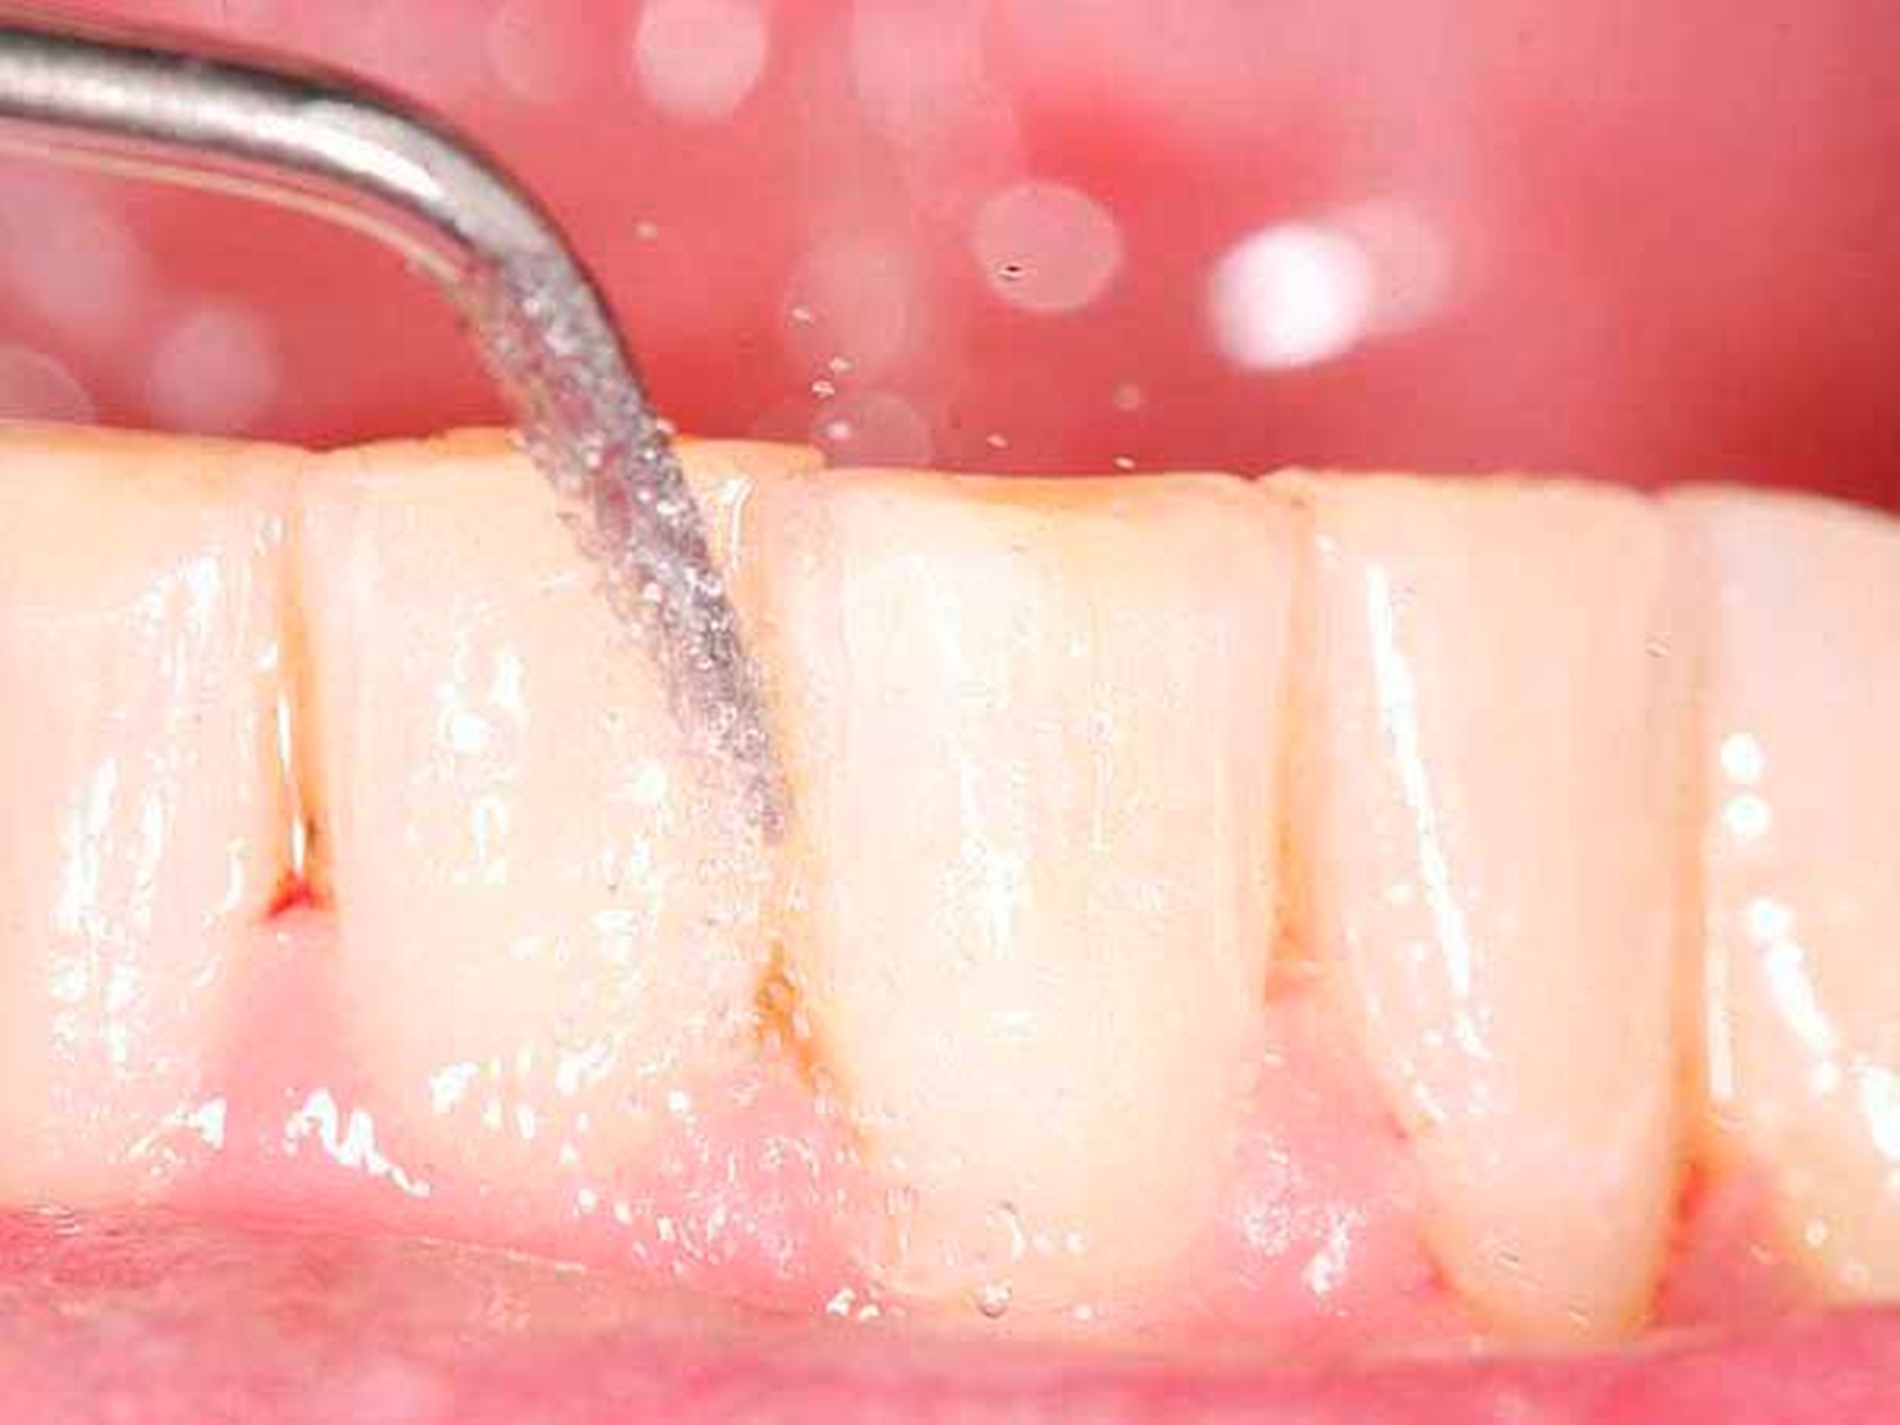

Für die subgingivale Instrumentierung kommen neben Handinstrumenten (wie Gracey-Küretten) auch maschinelle Instrumente mit Schall- oder Ultraschallantrieb infrage. In klinischen Studien zeigte eine Instrumentierung mit diesen Geräten keine deutlichen Unterschiede zwischen den verschiedenen Typen [Tunkel et al., 2002], zweckmäßigerweise können Hand- und maschinelle Instrumente kombiniert eingesetzt werden [Jepsen et al., 2011]. Eine übermäßige Bearbeitung der Wurzeloberflächen im Sinne einer klassischen Wurzelglättung sollte hierbei vermieden werden. Gleichzeitig ist eine Kürettage des Weichgewebes im Regelfall nicht indiziert [Heitz-Mayfield und Lang, 2013]. Neben einer seiten- oder quadrantenweisen Instrumentierung ist auch ein Full-Mouth-Scaling in einem Termin (oder an zwei Terminen innerhalb von 24 Stunden) möglich, allerdings ohne langfristig nachweisbaren klinischen Vorteil [Eberhard et al., 2015].

Als Alternative oder auch zusätzlich zu einer subgingivalen Instrumentierung mit Hand- oder Schall-/Ultraschallinstrumenten wurden optische Verfahren mit Lasern verschiedener Wellenlängen vorgeschlagen. Als der klassischen Instrumentierung ebenbürtig, wenn auch mit einem erhöhten Zeitaufwand verbunden, wird der Einsatz von Erbium:YAG-Hartgewebslasern angesehen [Sgolastra et al., 2012]. Andere Laser mit geringerer Wellenlänge eignen sich nicht so gut zur Entfernung mineralisierter Ablagerungen und werden daher ergänzend zur klassischen Instrumentierung eingesetzt. Bei diesem Einsatz ist unklar, ob ein zusätzlicher langfristiger klinisch relevanter Nutzen vorliegt [Sgolastra et al., 2013; Sgolastra et al., 2014]. Der adjuvante Einsatz einer photodynamischen Therapie zeigt ebenso wenig langfristige Erfolge bei stark heterogener Datenlage (siehe wissenschaftliche Stellungnahme von DG PARO und DGZMK). Ein Einsatz der PDT ist daher zum gegenwärtigen Zeitpunkt nicht anzuraten.

Von großem Interesse sind derzeit weiterhin subgingival eingesetzte Pulver-Wasserstrahl-Geräte. Mit gering abrasivem Pulver, häufig auf Glycin-Basis, können damit schnell und gründlich Biofilme, aber keine mineralisierten Ablagerungen entfernt werden [Flemmig et al., 2012]. Das Verfahren hat daher seine Stärke im Bereich der unterstützenden Parodontitistherapie, wo in der Regel keine ausgeprägten Konkremente zu erwarten sind. Für einen denkbaren Einsatz während der subgingivalen Instrumentierung liegen noch keine ausreichenden klinischen Daten vor, insbesondere ist wahrscheinlich die dem Verfahren immanente Gefahr eines Luftemphysems bei dem in der ersten Behandlungsphase oft noch stark aufgelockerten Gewebe (vgl. Abbildung 1) noch deutlich erhöht.